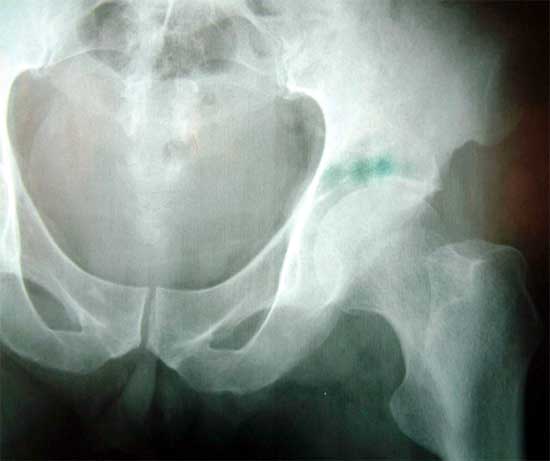

髋臼嗜酸性肉芽肿,臼顶骨破坏 刮除病灶,复合BMP的脱钙异体骨基质修复骨缺损,全髋关节置换术后1年